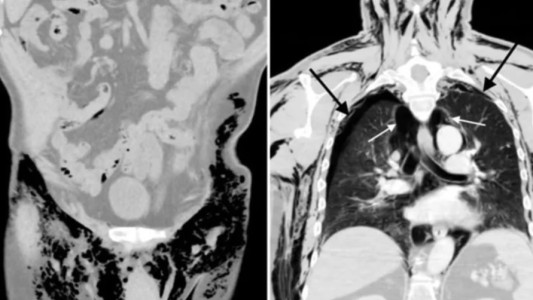

Ya encontraron al menos 30 víctimas del médico anestesiólogo que violaba mujeres mientras daban a luz